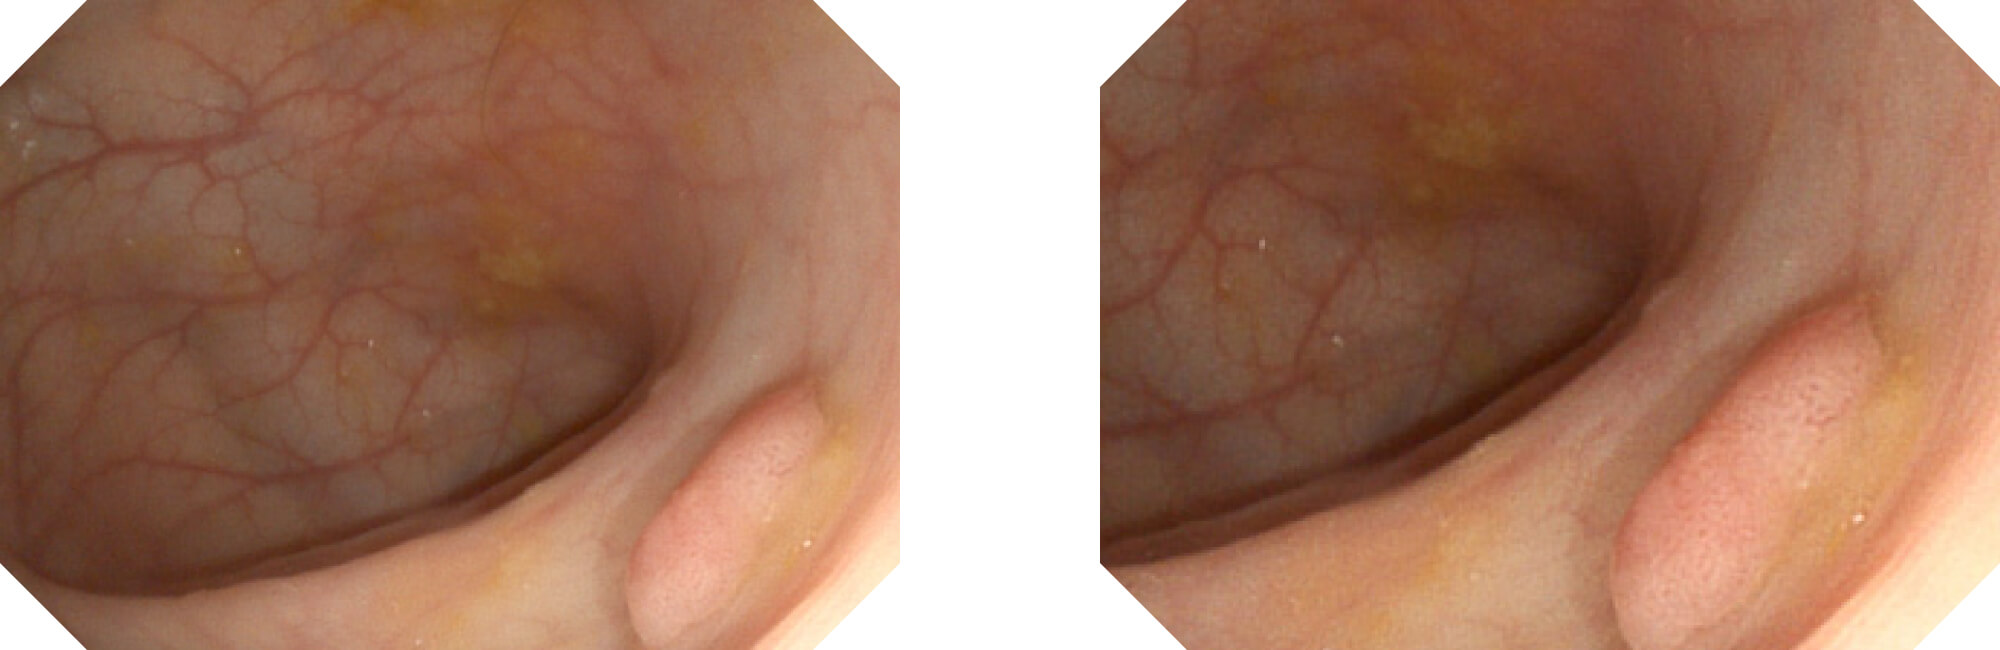

光电复合染色成像

(Versatile Intelligent Staining Technology)

利用了血红蛋白在不同波长吸收下系数不同的原理,设计的一种光学域滤波和数字域滤波结合的染色技术,既保证了图像亮度,又可增强黏膜血管的对比度,充分凸显早期病变的细微结构变化,为临床疾病的观察诊断提供更丰富的参考信息。